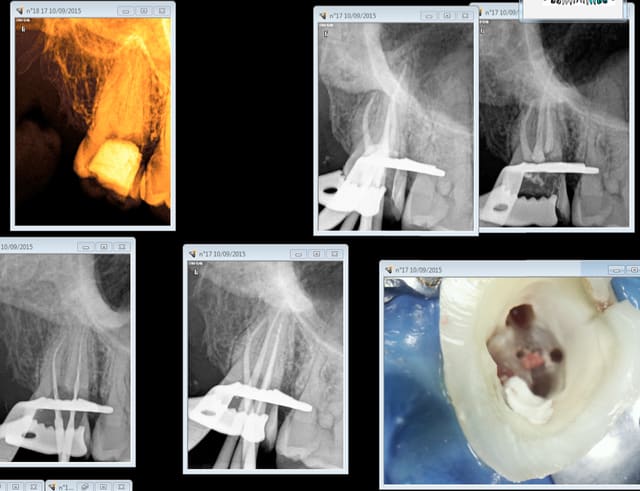

Autre exemple : 4 rétro coronaires ( 47 44 24 27) , endo 17 et 3 radios endos dans la meme séance.....

Capture d e cran 2015 09 10 19.19 - Eugenol

Capture d e cran 2015 09 10 19.22 - Eugenol